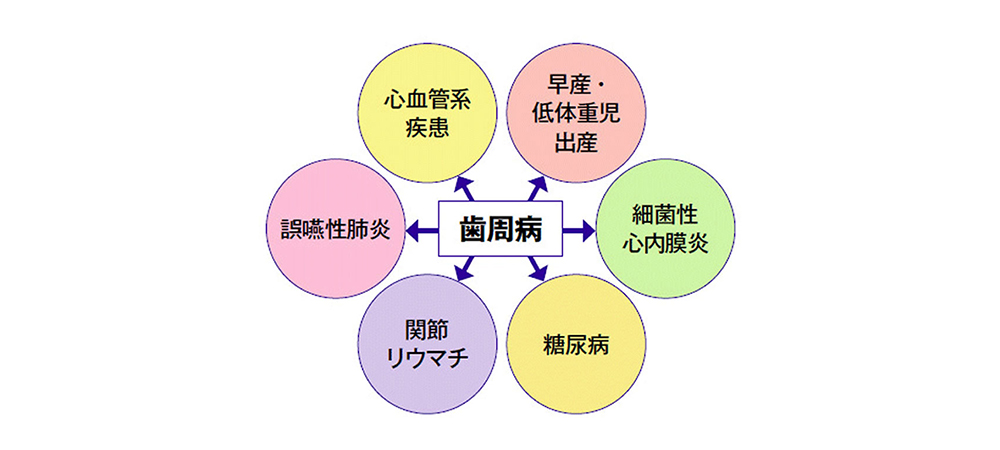

歯周病は様々な全身疾患リスクを高めます

歯周病はお口の中だけの問題ではありません。近年の研究により、歯周病がさまざまな全身疾患と関連していることが明らかになっています。

炎症を起こした歯茎から細菌や炎症物質が血流に入り込むことで、心筋梗塞や脳梗塞、糖尿病、誤嚥性肺炎、メタボリック症候群などのリスクが高くなると考えられています。また、妊娠中の方では、早産や低体重児出産との関連も報告されています。

歯周病対策は、単に歯を守るためだけでなく、全身の健康維持や大切なご家族の未来を守ることにもつながります。日頃の予防と早期治療に取り組むことが重要です。